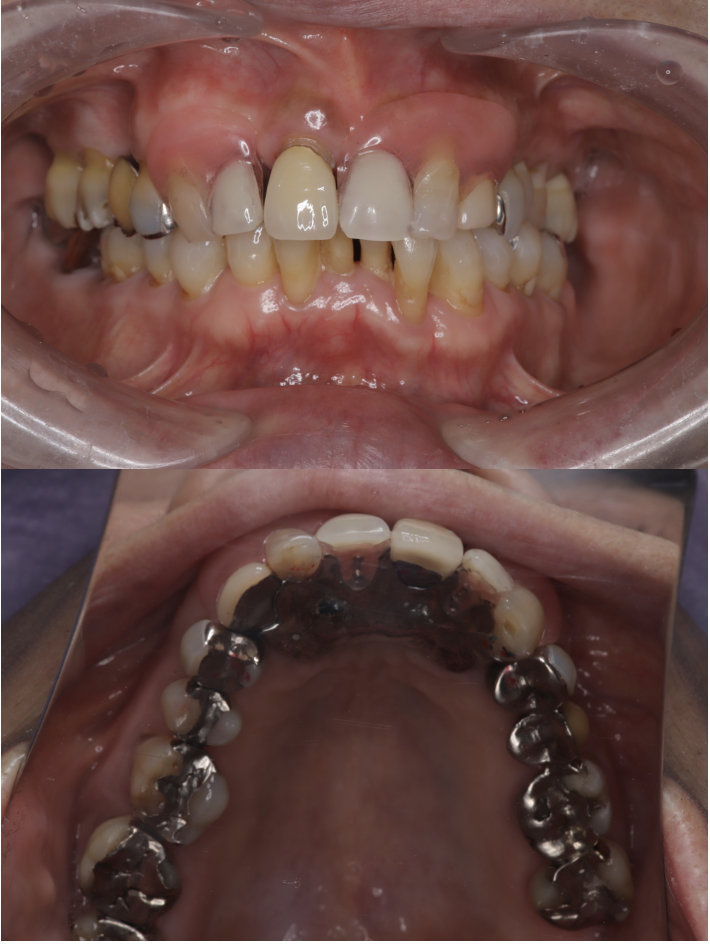

ノンクラスプ+金属床 2 +ノンクラスプ No.15

Before

After

| 治療方法 | ノンクラスプ、ノンクラスプ+金属床 入れ歯に金属のバネがある・ないの違いだけで口元の見た目は大きく変わります。金属のバネがない入れ歯「ノンクラスプデンチャー」は快適で自然な美しさのある入れ歯です。 金属床義歯は土台(床)の部分が金属で薄く作られる入れ歯です。保険の入れ歯に比べて厚みが出ないので、食べ物の温度を感じられ、食事を美味しく取ることができます。素材はコバルトクロムやチタンが使われます。 |

| 費用 | ¥99,000、¥269,000 |

| 通院回数 | 1ヶ月〜3ヶ月 |

| 備考 | 院長より 上下に入れ歯を作りました。上下とも見た目を重視してノンクラスプを選択されましたが、上は欠損が左右に渡り、大きくなり違和感が大きくなるので金属床を使用して違和感を減らしました。 |